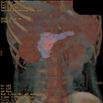

Pancreatic Axial

显示胰腺横断面影像